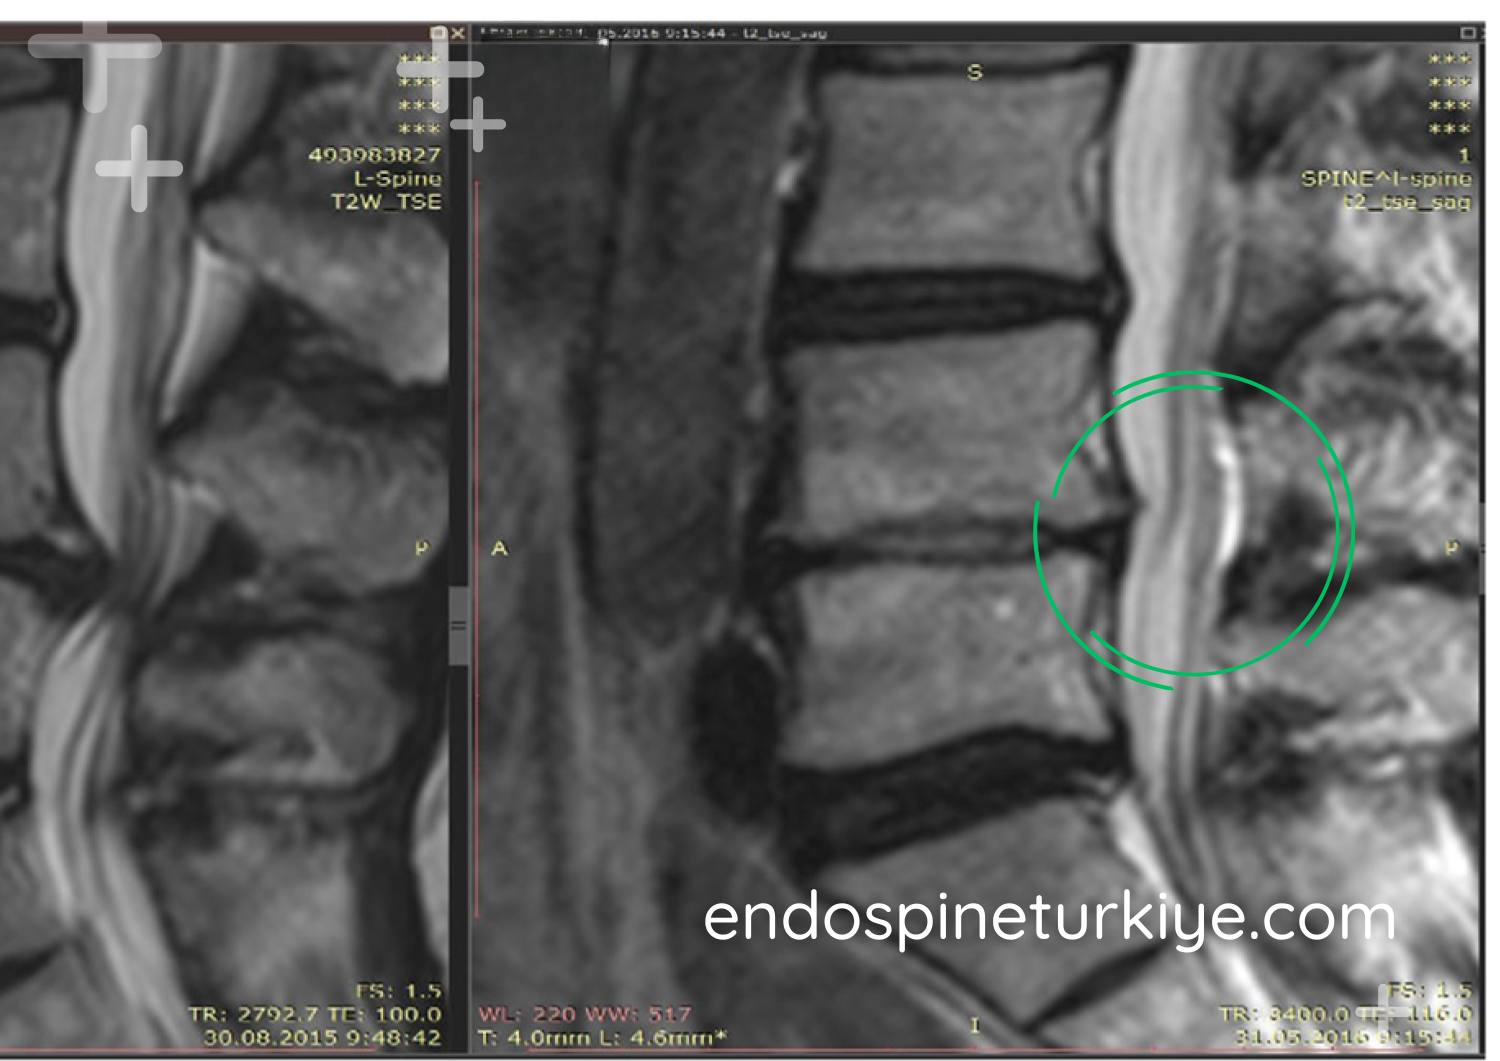

Ameliyat korkusundan son 1 yıl içinde her yöntemi denemiş ve sonuç alamamış biri olarak, Op. Dr. Rifat Saygın Altınağ'a tam kapalı endoskopik disk ameliyatı olalı 1 ay oldu. Birçok doktora gitmeme rağmen beni ikna eden tek kişi olduğu için güvenle ameliyatı kabul ettim. Çevremde açık ameliyat olup sorun yaşayanlar vardı. Rifat Bey'e gidene kadar tam kapalı ameliyatın mümkün olduğunu bilmiyordum. Şiddetli bacak ağrısından yürüyemeyen ben, şimdi normal hayatıma döndüm. Ameliyat sonrası 5 saat içinde hastanede korseyle yürümeye başladım. Kendimi o kadar iyi hissediyordum ki hastanede dolaştım. İyileşmeyi bekleyip yorum yazdım, bugün kontrolle tescillendi. Rifat Bey'e ve Merve Hanım'a teşekkürler.